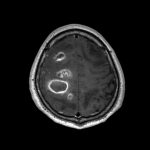

断層撮影

No.’25_45 手術前1

No.’25_45 手術前2